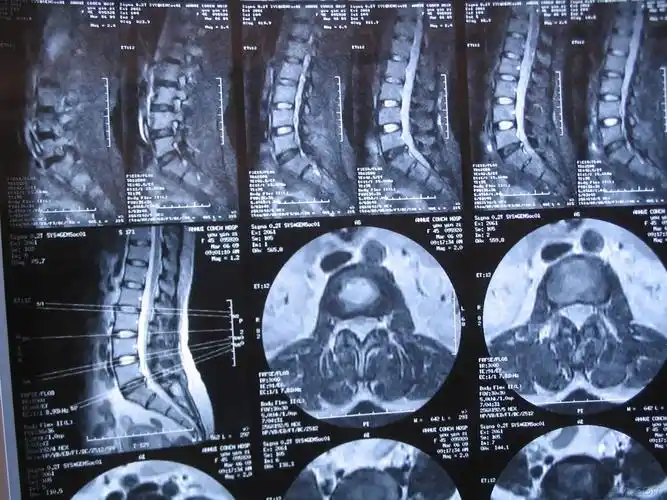

腰椎间盘ct平扫(l5-s1)

腰4-5椎间隙ct平扫显示腰4-5椎间盘突出及椎管狭窄.